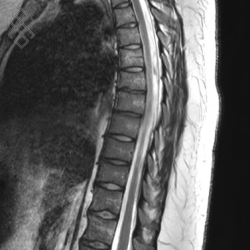

IRM Médullaire

La durée moyenne de l'examen est de 25 min. Dans le cas d'une injection, le manipulateur en radiologie vous administrera le produit de contraste. Vous entendrez un bruit caractéristique à l'IRM faisant penser à un marteau piqueur.